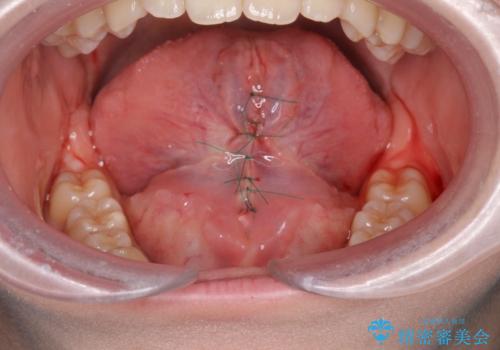

発音がしやすくなり、治療の結果に喜んでいただくことができました。

- 外科手術のため、術後に出血、痛みや腫れ、違和感を伴います

- 口腔内の状態によっては適応できないことがあります